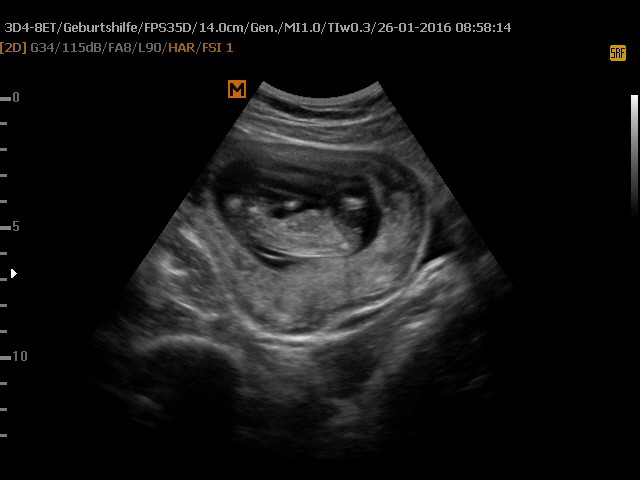

Wczoraj miałam wizytę - wszystko ok, ciąża troszkę większa, bo wszytskie pomiary pokazywały na 12+4, wszystko ok, więc ulga wielka, bardzo długo mi robił usg, mierzył i wszystko ok. Kolejne badania do zrobienia na tokspolazmoze a już sama chciałam sobie robić. Kolejna wizyta za 3 tygodnie. pokazuje zdjęcie z usg, po lewejrączka przy główce, na drugim nóżki i brzuszek![]()

dał mi zdjęcie i mówi :ma Pani swoje nóżki i rączki